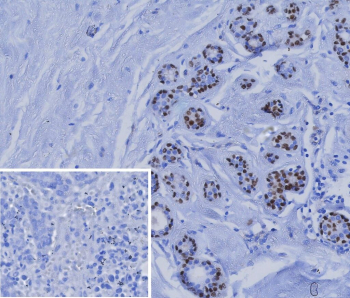

Immunohistochemistry analysis of Transcription factor SOX10 antibody (clone rSOX10/991) in formalin-fixed, paraffin-embedded human breast carcinoma tissue. Distinct nuclear staining is observed in tumor cells, consistent with SOX10 expression. The inset shows PBS used in place of primary antibody as a negative control, demonstrating absence of specific staining. Antigen retrieval was performed by heating tissue sections in 10 mM Tris with 1 mM EDTA, pH 9.0, for 45 minutes at 95oC followed by cooling at room temperature for 20 minutes.